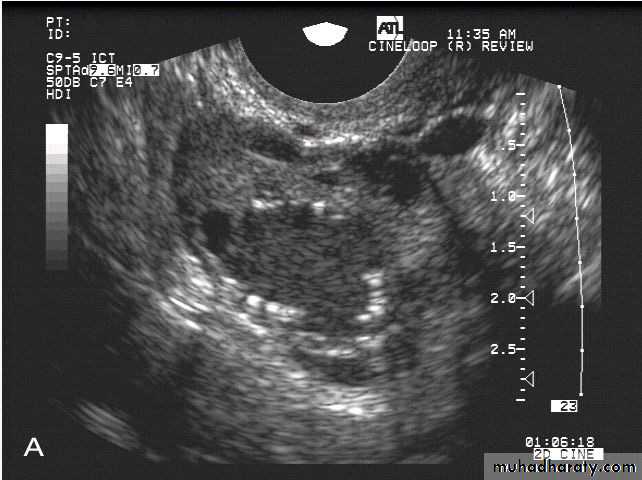

Ovarian hyperstimulation syndrome (OHSS):

This young adult female patient was examined to evaluate the uterus and ovaries. She was under treatment for infertility and was using gonadotropins. Ultrasound images of the ovaries show grossly enlarged ovaries with large cysts (measuring 2.6 to 3 cms.) in both ovaries. These ultrasound findings are diagnostic of OHSS or ovarian hyperstimulation syndrome.

• Ovarian hyperstimulation syndrome (OHSS):

The ultrasound image again show hyperstimulated ovaries. Both ovaries are grossly enlarged and cystic.